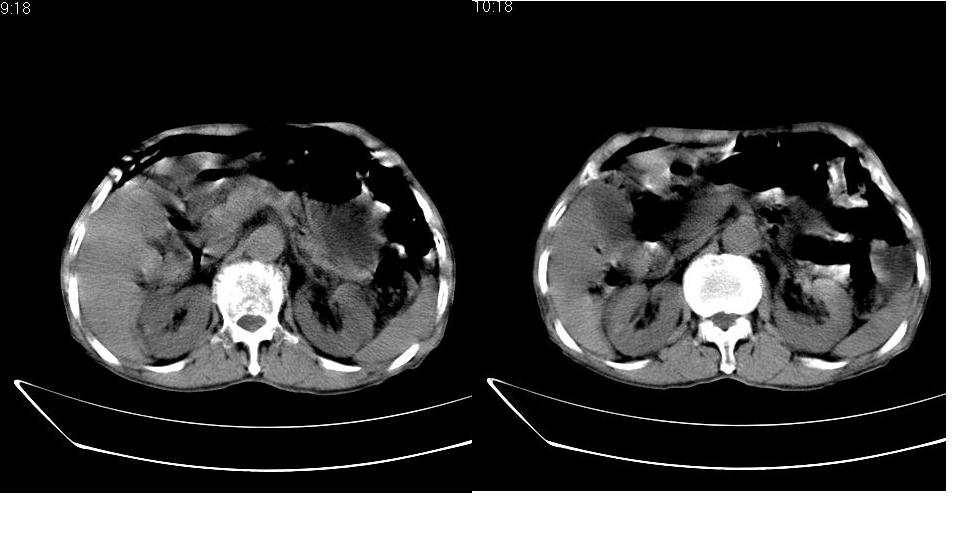

男,76岁,上腹部疼二天来就诊,彩超提示肝左叶占位,随后做上腹部ct平扫,今天做上腹部ct增强扫描,手工推药,效果不好,请谅解。

肝左叶s4肿块强化形式大概是:慢进慢出,逐渐强化----考虑血管瘤/腺瘤?{动脉期应更提前扫}。

1)肝右叶前段低密度灶,不排除肝癌可能;建议查afp。2)右肾上极囊肿。

肝内胆管积气扩张,胆囊增大,肝右前叶低密度灶,逐渐强化,一元论,胆系感染,局限性肝脓肿;右肾囊肿。

考虑肝s4段肝脓肿可能?未排除肝癌。右肾上极囊肿。